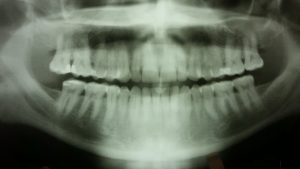

How safe are X-rays?

Different sources of radiation include the sun, minerals in the soil, appliances in your home, and dental X-rays — these can damage the body’s tissues and cells and possibly lead to the development of cancer. Fortunately, the dose of radiation you are exposed to during the taking of X-rays is extremely small.

Advances in dentistry over the years have lead to the low radiation levels emitted by dental X-rays. Some improvements are, higher speed X-ray films that require shorter exposure time compared with older film speeds to get the same results, and the use of film holders that keep the film in place in the mouth, which prevents the film from slipping and having to take another x-ray. Also, the use of lead-lined, full-body aprons, this protects the body from stray radiation. In addition, federal law requires that X-ray machines be checked for accuracy and safety every two years, with some states requiring more frequent checks.​